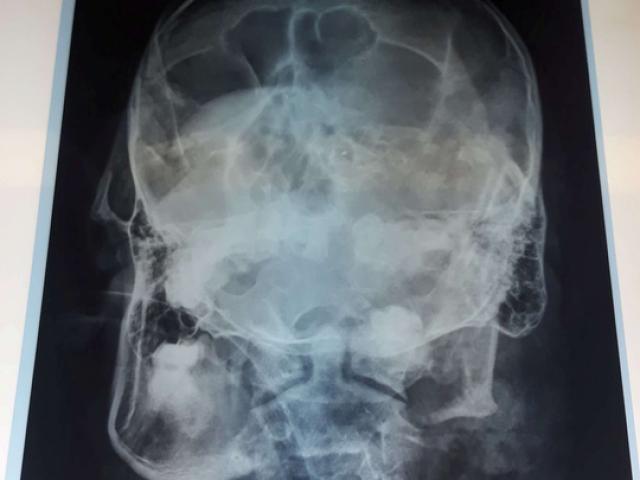

Ngày 4-12, ông Bùi Chí Hiếu (SN 1986), Phó Chỉ huy trưởng Ban Chỉ huy Quân sự (CHQS) phường Đoàn Kết, thị xã Ayun Pa, tỉnh Gia Lai - nghi phạm dùng súng quân dụng bắn chết bà Kpah H’Ven (SN 1987), Phó Chủ tịch HĐND phường này - vẫn đang được điều trị tại Bệnh viện Đa khoa tỉnh Gia Lai. Bác sĩ Phạm Bá Mỹ, Giám đốc Bệnh viện Đa khoa tỉnh Gia Lai, cho biết Hiếu bị dập nát phần cằm, vùng mặt nhưng không tổn hại đến não. Sau ca phẫu thuật, sức khỏe Hiếu đã ổn định, tiến triển tốt.